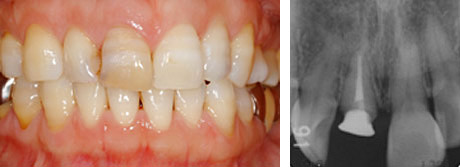

Before

この症例は、折れてしまった前歯をインプラントで治療した例です。

治療前:右上前歯の破折で患者さんは来院されました。